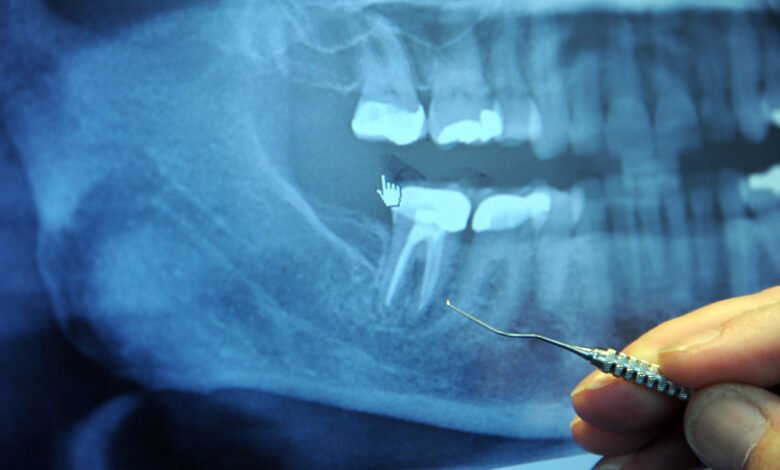

Toothache can result from a range of dental issues, some mild and others more severe. Common causes include tooth decay, gum infections, dental abscesses, and cracked teeth. Each condition can trigger different sensations, such as sharp pain, throbbing discomfort, or sensitivity to hot and cold foods. Identifying the root cause is crucial before relying solely on painkillers like paracetamol.

Persistent or severe tooth pain can indicate an infection or a more serious dental problem that requires prompt attention. While paracetamol helps manage the discomfort, it does not treat infections or repair structural dental issues. Understanding the cause of the pain ensures that temporary relief does not delay necessary professional treatment.